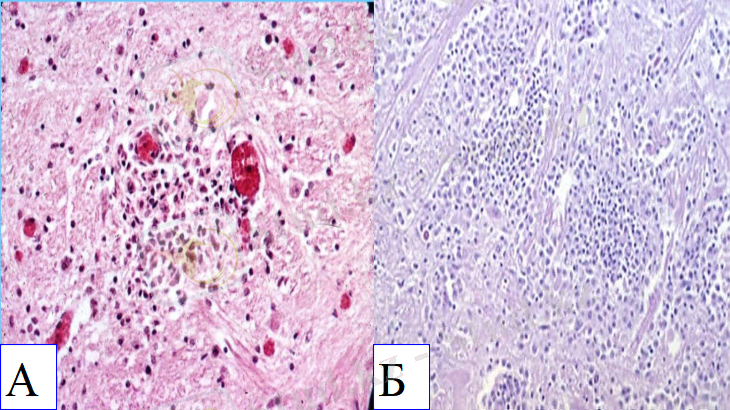

Мидағы қабыну көріністері: В. Лимфоцит, макрофаг пен плазмоциттерден тұратын анық периваскулярлы қабынған инфильтрат (ірі қара мал)

С. Нейропилдегі дегенерацияланған нейтрофилдерден тұратын қабынған инфильтраттардың майда ошақтары (қой)

D. Нейрофилдерден тұратын мультифокальды инфильтраттармен байланысқан көптеген базофильды бактериялардың нейропилдегі құрылымы

Мида майда НЕКРОЗ ошақтары кездеседі. [2]

Ми: майда некроз ошақтары, іріңді қабыну, периваскулярлы инфильтрация